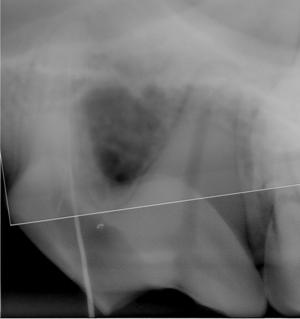

● 歯の破折 4 : 切 歯 の 破 折

真ん中の歯が折れています。

折れた部分を黄色でトレースしています。